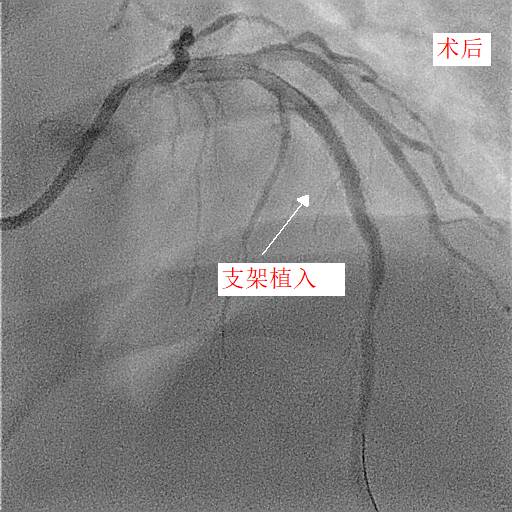

第二天,小天和父亲同一天接受冠脉造影和手术治疗,冠脉造影进一步明确了:小天冠状动脉回旋支完全堵死、前降支90%堵塞,而右冠状动脉也仅有一丝血流通过。造影中医生发现,小天的血管狭窄已经有一段时间,其中的右冠状动脉已经产生了侧支循环。随后医生在患者右冠状动脉里放入了两个支架,恢复了血流。

康慧元医生说:“患者的三条心脏血管都严重堵塞,很容易发生急性心梗甚至猝死,手术先开通慢性堵塞的右冠状动脉,保证心脏有足够的血流。”

两天后,医生再次手术解决了左前降支的问题,至于回旋支因为先天血管发育较小,可暂时观察,后续再处理。